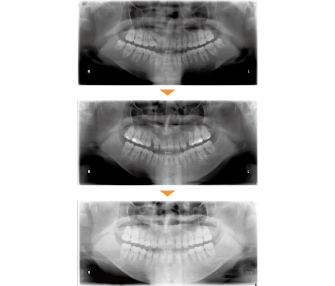

| 主訴 | 前歯が出ている |

| 年齢・性別 | 35歳 / 女性 |

| 治療方針 | 叢生も前歯の突出も大きいケース。小臼歯抜歯だけでは改善できないため、大臼歯の抜歯も行なった。 |

| 抜歯部位 | 上下顎左右小臼歯、左上第1大臼歯(計5本) |

| 使用装置 | マルチブラケット装置 |

| 治療期間 | 36か月 |

| リテーナー | 上顎インビジブル、フィックス、下顎インビジブル |

| 費用 | 885,000円(税別) |